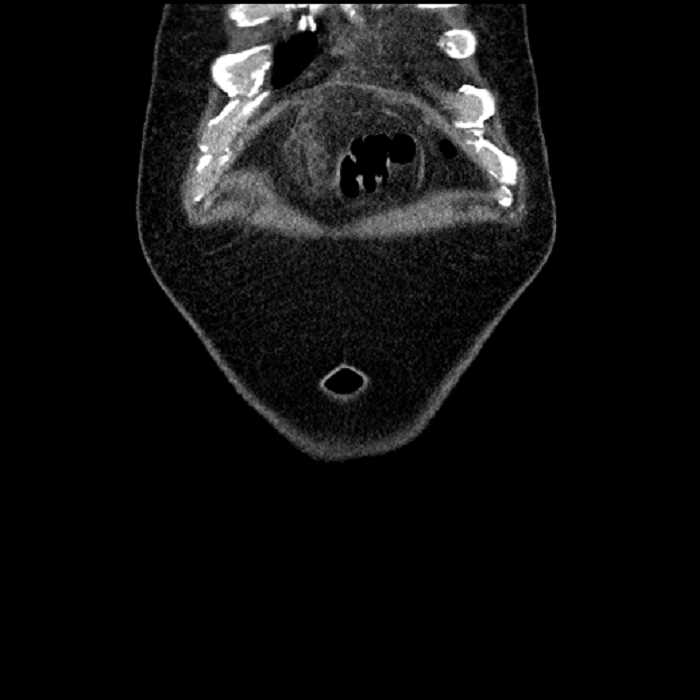

Acute sigmoid diverticulitis complicated by a small contained perforation and a large abscess in the right hepatic lobe. Additional small subcapsular abscesses along the anterior margin of the left hepatic lobe.

• The classic CT imaging appearance is a double target sign with internal low density surrounded by an internal enhancing rim (capsule) and a low density external rim (edema)

Hepatic abscess showing the double target sign with low density internally surrounded by a thin inner enhancing rim (red arrow) and ill-defined outer low density rim (yellow arrow). Blue arrow indicates an internal septation. Red arrows: additional smaller subcapsular abscesses. Red arrow: focal contained perforation associated with diverticulitis.